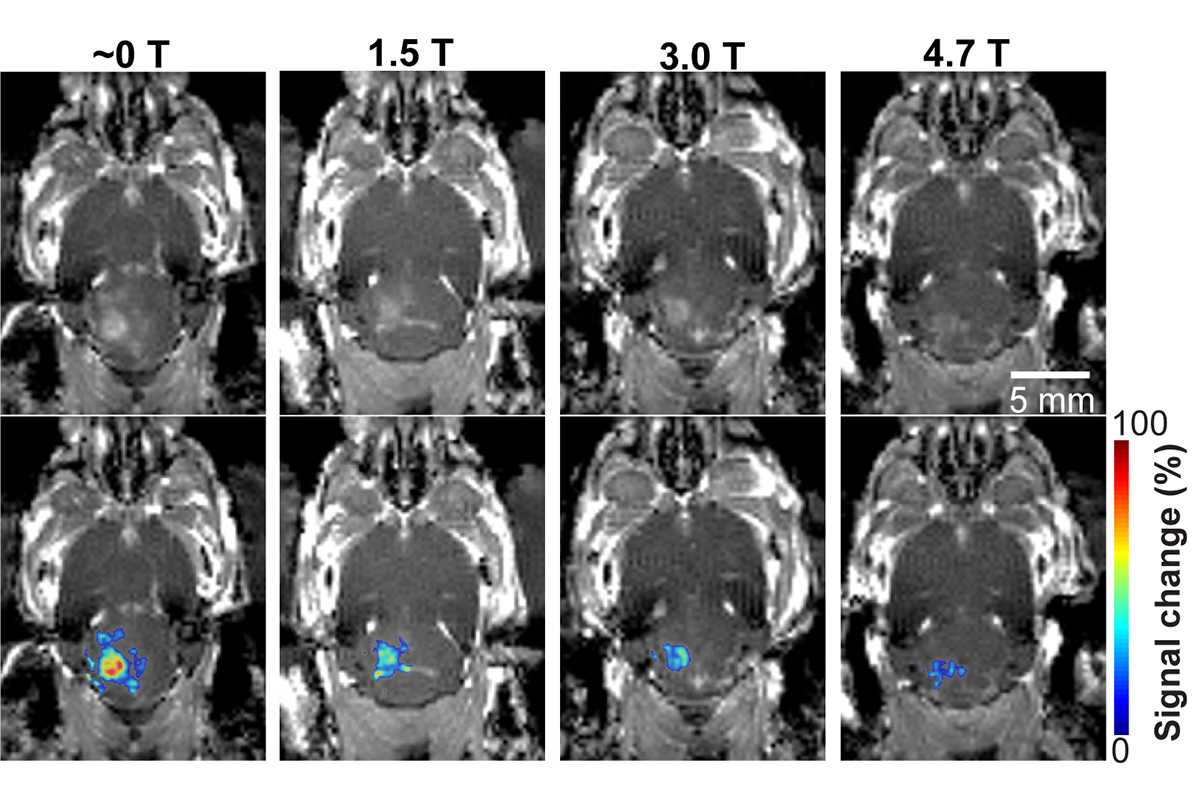

In new research published July 6, 2021, in Radiology, Hong Chen and her lab at Washington University in St. Louis have found for the first time that the magnetic field of the MRI scanner decreased the BBB opening volume by 3.3-fold to 11.7-fold, depending on the strength of the magnetic field, in a mouse model.

Chen, associate professor of biomedical engineering in the McKelvey School of Engineering and of radiation oncology in the School of Medicine, and her lab conducted the study on 30 mice divided into four groups. After the mice received the injection of the microbubbles, three groups received focused-ultrasound sonication at different strengths of the magnetic field: 1.5 T (teslas), 3 T and 4.7 T, while one group never entered the magnetic field.

They found that the activity of the microbubble cavitation, or the expansion, contraction and collapse of the microbubbles, decreased by 2.1 decibels at 1.5 T; 2.9 decibels at 3 T; and 3 decibels at 4.7 T, compared with those that had received the dose outside of the magnetic field. In addition, the magnetic field decreased the BBB opening volume by 3.3-fold at 1.5 T; 4.4-fold at 3 T; and 11.7-fold at 4.7 T. None of the mice showed any tissue damage from the procedure.